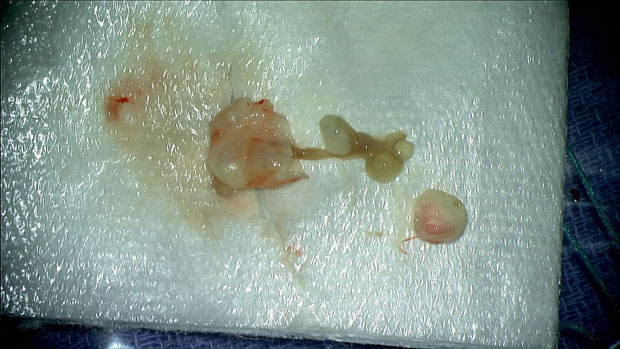

Izvađena pantljičara, foto Mount Sinai Health System

– Svi smo se čudili i pitali: Šta je ovo. Pomalo smo bili šokirani i iznenađeni izgledom – prisjeća se Rasuli za Vašington post. Hirurzi su odstranili masu, a onda je i stavili pod mikroskop i shvatili da se radi o larvi pantljičare.